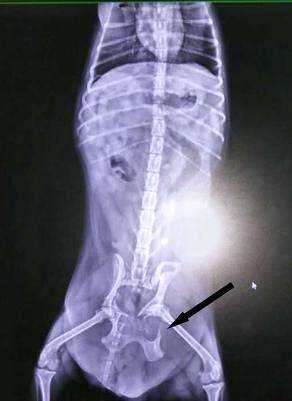

X光影像学诊断:正位和侧位评估骨盆的损伤,显示骨折面,膀胱X光片和尿道造影显示有无尿道和膀胱损伤。

另一车祸犬的骨盆骨折,箭头所指为骨折处。

进行尿道造影,显示腹腔内大量造影液,提示尿道腹腔段破裂,或者膀胱破裂。